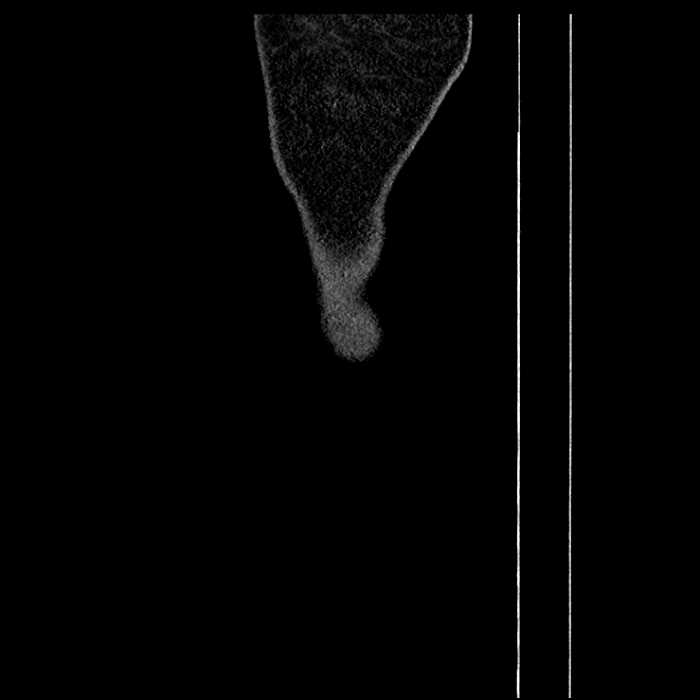

• Mild mural thickening of a segment of the sigmoid colon with adjacent fat stranding and a 1.5 cm fluid and gas collection along the tip of an inflamed diverticulum

Hepatic abscess showing the double target sign with low density internally surrounded by a thin inner enhancing rim (red arrow) and ill-defined outer low density rim (yellow arrow). Blue arrow indicates an internal septation. Red arrows: additional smaller subcapsular abscesses. Red arrow: focal contained perforation associated with diverticulitis.